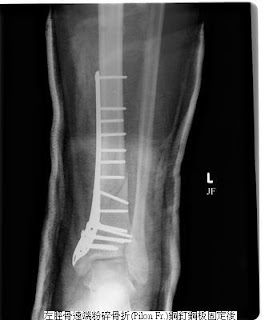

骨折開刀,用來固定的鋼釘、鋼板【(泛稱);目前用的都是合金材質】,在骨折癒合後,要不要拿掉?

早期骨科教科書或老師都說:骨折在癒合後,這些內固定金屬都應該要拿掉(取出)。要拿掉,最大的理由是:這些金屬對身體言 是不能吸收的「異物」,異物的存在,在身體免疫力變差時,有潛在會變成感染病灶的可能;另者,鋼釘、鋼板有的在骨折癒合後,會形成局部組織空間的擠壓或造成刺激,甚至使表皮、軟組織潰瘍;另外,有些情況,像鋼釘穿入關節腔,會妨礙關節活動、造成軟骨磨損,導致骨關節炎;而金屬也在作核磁共振或電腦斷層檢查時,會造成影像的干擾…..;這些,都是存留鋼釘鋼板可能有的不良後果,因此把鋼釘鋼板拿掉,邏輯上,好像是房子蓋好就把膺架拆除一樣,看似很自然的事。但”拿掉”也意味著還要再開一次刀,對病人言是要再面對一次麻醉與手術的風險,也須再付出醫療成本。 那麼,鋼釘鋼板是不是一定要拿呢?